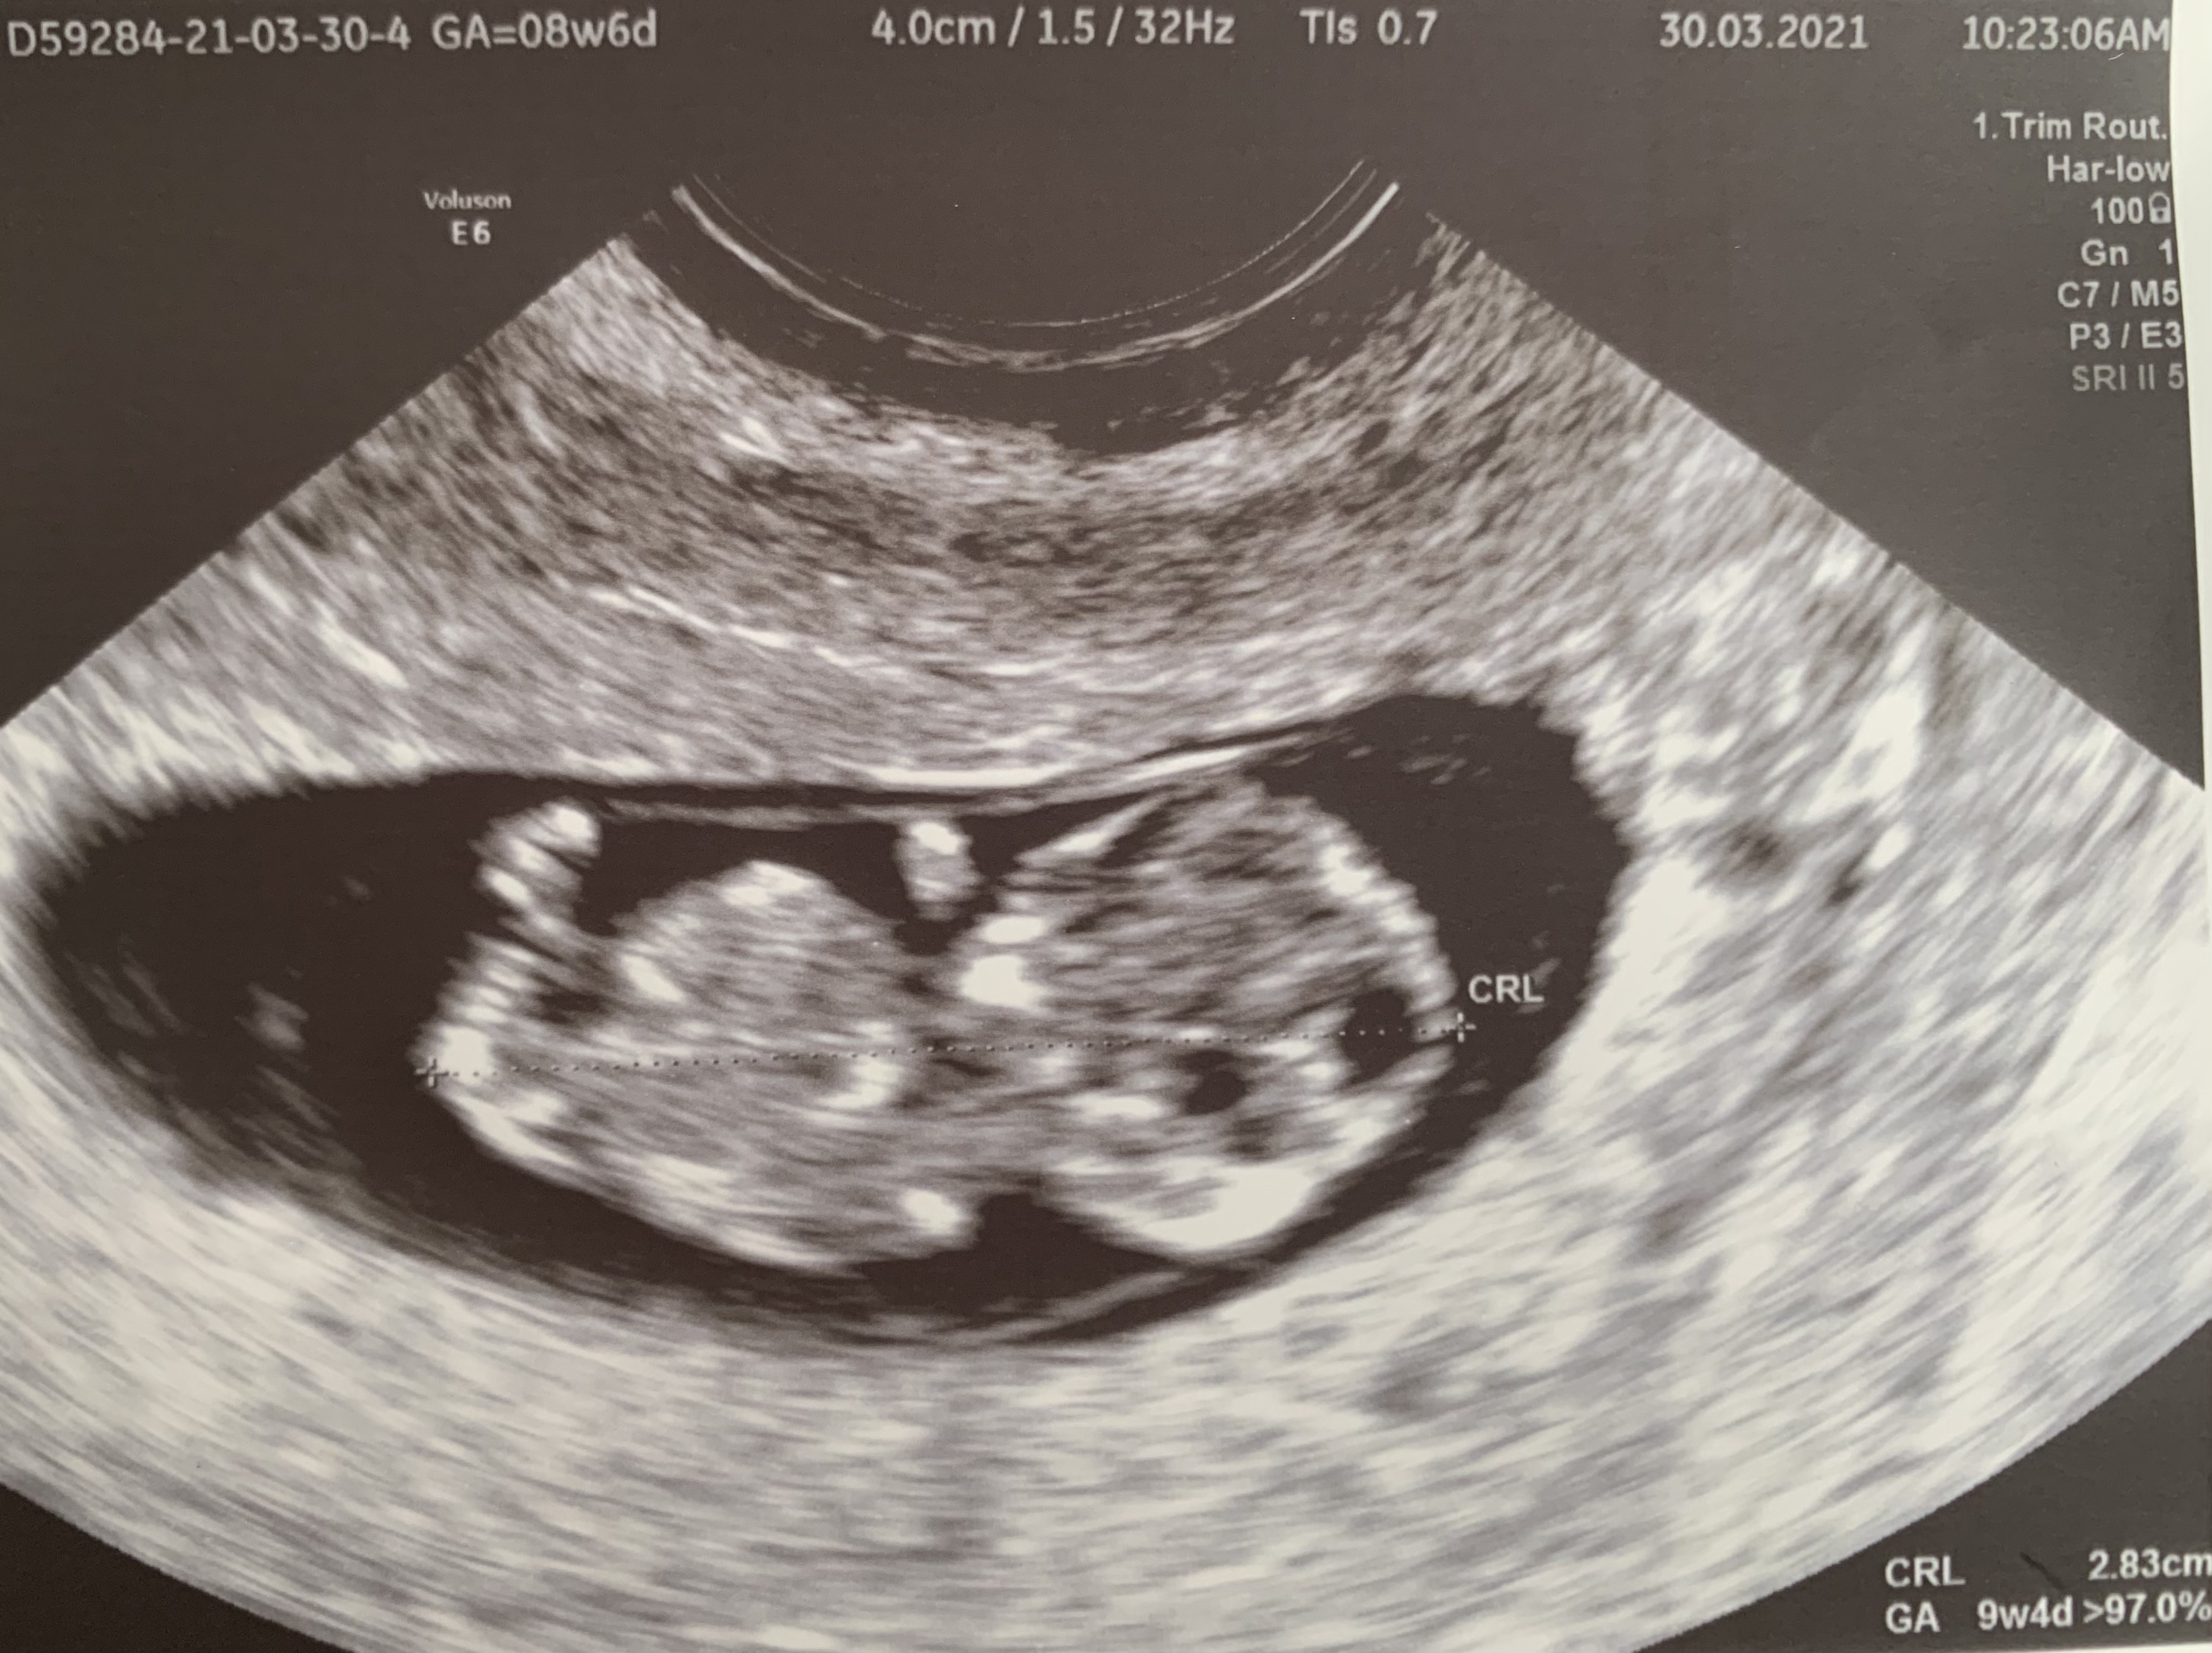

Już po wizycie ... dzidzia już nie wyglada jak fasolka ☺️ Na dzień dzisiejszy wSzytsko wyglada bardzo dobrze ☺️

Załączniki

• 429A3890-65FA-40EE-8C07-009AC7B46639.jpeg

429A3890-65FA-40EE-8C07-009AC7B46639.jpeg

1,3 MB · Wyświetleń: 146